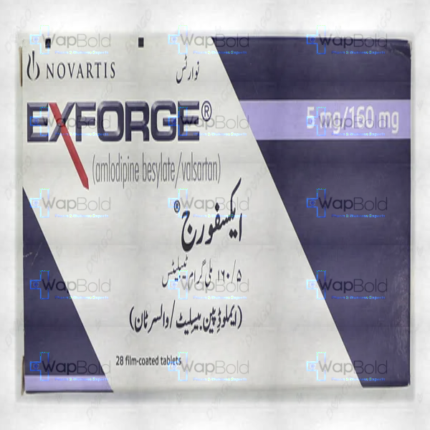

Amstan Tablets 10/160Mg (1 Box = 1 Strip)(1 Strip = 14 Tablets)

Avaam 10/160Mg Tablets 14S

₹150.00